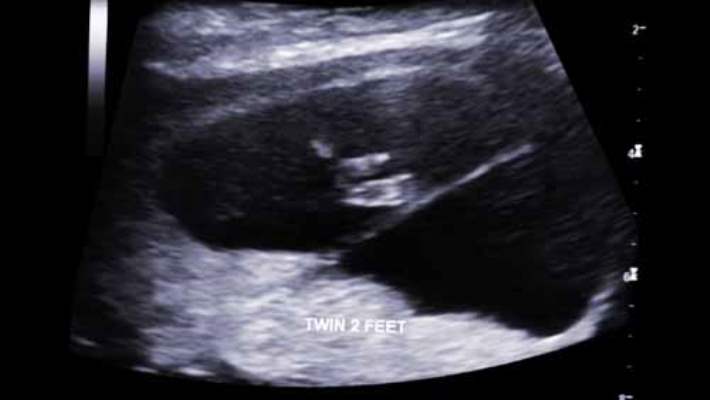

Ultrason muayenesi için, bir muayene masasına sırtüstü yatarsınız. Doktorunuz veya teknisyen, ses dalgalarını göndermek ve yansımaları toplamak için ufak, çubuk benzeri bir cihazı vajinanıza yerleştirir. Yansıyan ses dalgaları, dijital olarak bir ekran üzerindeki görüntülere dönüştürülür. Doktorunuz veya teknisyen bu görüntüleri, bebeğinizin boynunun arkasında bulunan dokudaki boş alanı ölçmek için de kullanır.

Ultrason bir saat kadar sürebilir. Acı vermez ve günlük aktivitelerinize hemen dönebilirsiniz. Test sonuçları genellikle bir haftadan önce hazır olur.